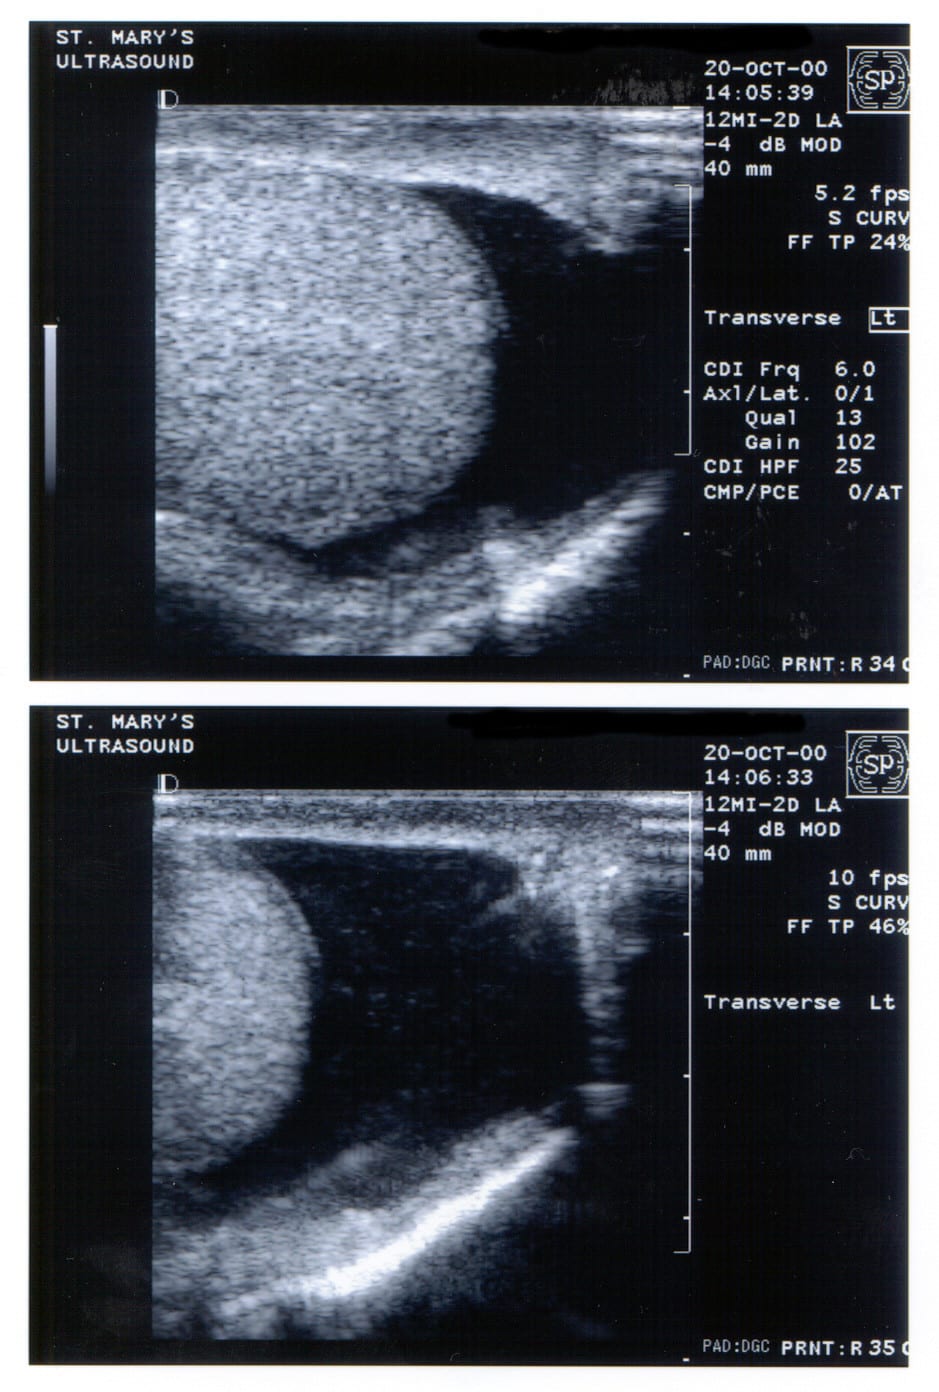

Ryan Stephens went to his primary care doctor, Dr. Audra Ford at Kaiser Permanente West Cobb Medical Center, reporting a mass on his left testicle. Dr. Ford did not perform a physical exam. She also neglected to order an ultrasound to investigate possible testicular cancer, although Kaiser’s own practice guidelines required her to do so. Instead, Dr. Ford referred Stephens to Kaiser urologist Dr. Barry Mason for further evaluation.

At the follow up appointment, Dr. Mason examined Stephen’s scrotal contents with his hands but testified he did not feel an unusual mass as Stephens initially reported. Dr. Mason also neglected to order an ultrasound to examine the testicles, but instead sent Stephens home with directions to “self-examine” for possible cancerous masses.

Courtney Stephens. “When a 24-year-old male goes to the doctor and reports feeling an unusual mass on his testicle, it is presumed to be cancer until proven otherwise,” said Bell. “The ‘gold standard’ for diagnosing testicular cancer is an ultrasound imaging study, a simple, safe and reliable test. For reasons that are still a mystery, neither of Ryan’s two treating doctors at Kaiser ordered this simple test. As a result, Ryan’s cancer went undiagnosed for over six months, until it was too late to save him.”